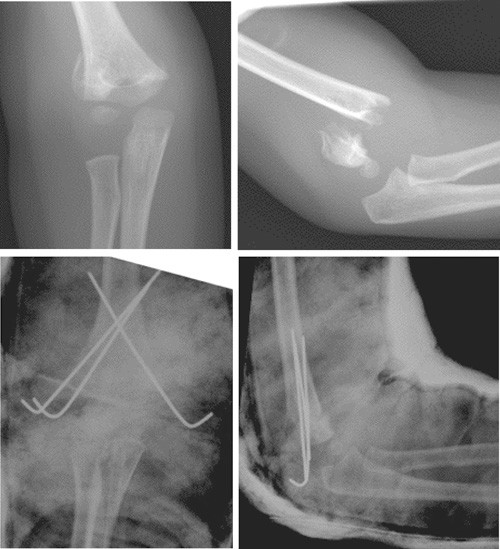

Suprakondylære humerusfrakturer hos barn klassifiseres i dag etter Gartlands klassifikasjon (fig 1) (8). Denne klassifikasjonen har god intra- og interobservatør reliabilitet (9). Gartland type 1 er en udislokert fraktur. Type 2 er en dislokert fraktur med intakt bakre cortex. Disse frakturene er av ren ekstensjonstype, ettersom den posteriore cortex stabiliserer bruddet i rotasjon. Type 3 er en helt dislokert fraktur uten kontakt mellom bruddfragmentene og har ofte rotasjonsfeilstilling i tillegg til ekstensjonsfeilstilling. Disse bruddene er assosiert med nevrovaskulær skade. Det er rapportert pulsløs ekstremitet i opptil 20 % av Gartland type 3-frakturer (4).

Perkutan pinneteknikk ble beskrevet første gang av Judet i 1947 (19), og er den dominerende behandlingsmetoden i verden i dag (14, 20) – (22). Bruddet reponeres lukket og fikseres med Kirschner-pinner som føres inn perkutant. Pinnene settes enten i kryss fra hver kondyl og opp i diafysen, eller kun fra lateralsiden. I tillegg immobiliseres bruddet i gips. I Skandinavia har man hatt lang tradisjon for både strekkbehandling og perkutan pinneteknikk (10, 23). Fordelen med perkutan pinning sammenliknet med immobilisering i gips alene er bedre kontroll over bruddfragmentene, og dermed bedre reposisjon uten å måtte immobilisere albuen så flektert at faren øker for kompartmentsyndrom i anteriore fossa med risiko for påfølgende Volkmanns kontraktur (24). Det er vist at at perkutan pinning er billigere enn strekkbehandling pga. kortere liggetid i sykehus, og at behandingsmetoden gir lavere risiko for varusfeilstilling (21). Ulempene ved metoden er hovedsakelig pinneinfeksjon og risiko for iatrogen skade av nevrovaskulære strukturer, hovedsakelig n. ulnaris ved bruk av medial pinne (25). Dyp infeksjon er meget sjeldent, og forekommer i under 0,2 % av tilfellene (26). Antibiotikaprofylakse i forbindelse med operasjonen er derfor ansett som unødvendig og blir ikke gitt rutinemessig (26).

Det er uenighet i litteraturen om den optimale pinneplasseringen. En kadaverstudie fra 1994 utført av Zionts og medarbeidere viste at kryssende pinner er mer biomekanisk stabile enn to laterale pinner (27), men man har ikke kunnet påvise klinisk konsekvens av dette (20, 22, 28). Hovedargumentet mot kryssende pinner er risiko for skade på n. ulnaris (29). Komplette utfall av n. ulnaris forekommer sjelden, og skyldes som regel skade på nerven i forbindelse med frakturen eller reposisjonen. Mindre alvorlige utfall/nevrapraksi går som regel tilbake etter fjerning av pinnen (26, 30). En metaanalyse fra 2007 konkluderte med at valg av pinnekonfigurasjon betyr lite for komplikasjonsrisikoen og kan derfor være opp til den enkelte kirurg (25). På Akershus universitetssykehus har vi som rutine å bruke kryssede pinner. Det er uklart hvor mange pinner som er nødvendig (31). I de fleste studier har man benyttet to pinner som standard, og latt kirurgen vurdere behovet for flere pinner peroperativt. I et retrospektivt materiale på 112 brudd fra Akershus universitetssykehus var 67 % operert med to kryssede pinner, 26 % med tre pinner (to laterale og en medial) og 5 % med fire pinner (to laterale og to mediale) (5).